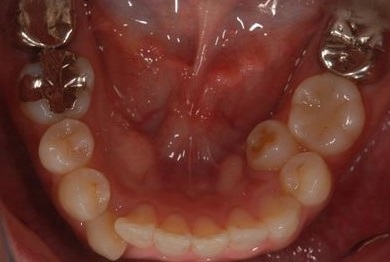

| カテゴリー | 【セラミック治療】 | ||||||||||||||||||||||||||||||||

| 性別/年齢 | 女性 / 31歳 | ||||||||||||||||||||||||||||||||

| 治療方針 | セラミック治療により、審美的回復を行う。 | ||||||||||||||||||||||||||||||||

| 治療内容 | CAD/CAMオールセラミッククラウン1本(オールセラミック用土台1本)、オールセラミッククラウン2本(オールセラミック用土台2本) | ||||||||||||||||||||||||||||||||

| 総治療費 | 341,775円 | ||||||||||||||||||||||||||||||||

| 治療期間 | 10ヶ月 |